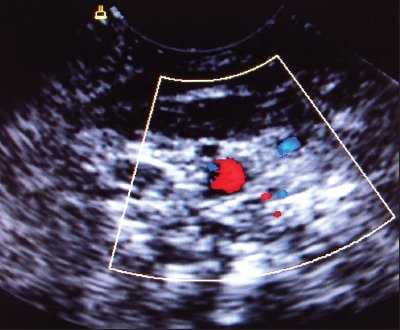

При аномалии расположения отмечалось обратное расположение сосудов: внутренняя яремная вена находилась более глубоко и медиально по отношению к сонной артерии. Как правило, диаметр внутренней яремной вены при аномалии расположения сосудов был существенно меньше диаметра сонной артерии (рис. 5). Все аномалии имели односторонний характер.

Рис. 5. Аномалия расположения и размера внутренней яремной вены (вена располагается медиальнее артерии, ее размер существенно меньше размера артерии).